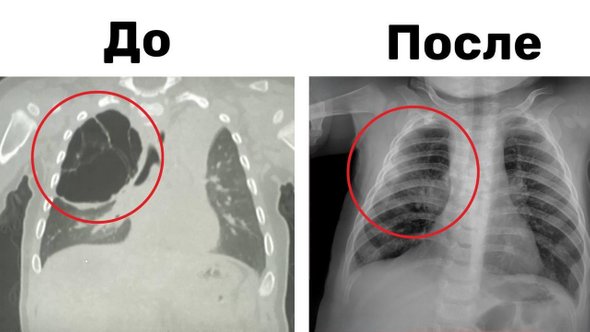

Врачи удалили 8-месячному ребенку 15-сантиметровую кисту, появившуюся в легком после простуды

По информации медиков больницы, младенец поступил в центр с кистозным образованием в легком, которое было обнаружено во время воспалительного процесса, вызванного на фоне обычной простуды. Компьютерная томография показала, что киста, по сравнению с телом пациента, была огромной и занимала большую часть правого легкого. Новообразование сдавливало здоровую ткань органа и не давало ему полноценно работать и развиваться.

Детские хирурги-пульмонологи провели ребенку торакоскопическую операцию. Врачи смогли без разреза аккуратно удалить кисту вместе с пораженной частью верхней доли правого легкого. Операция длилась около часа и прошла успешно.